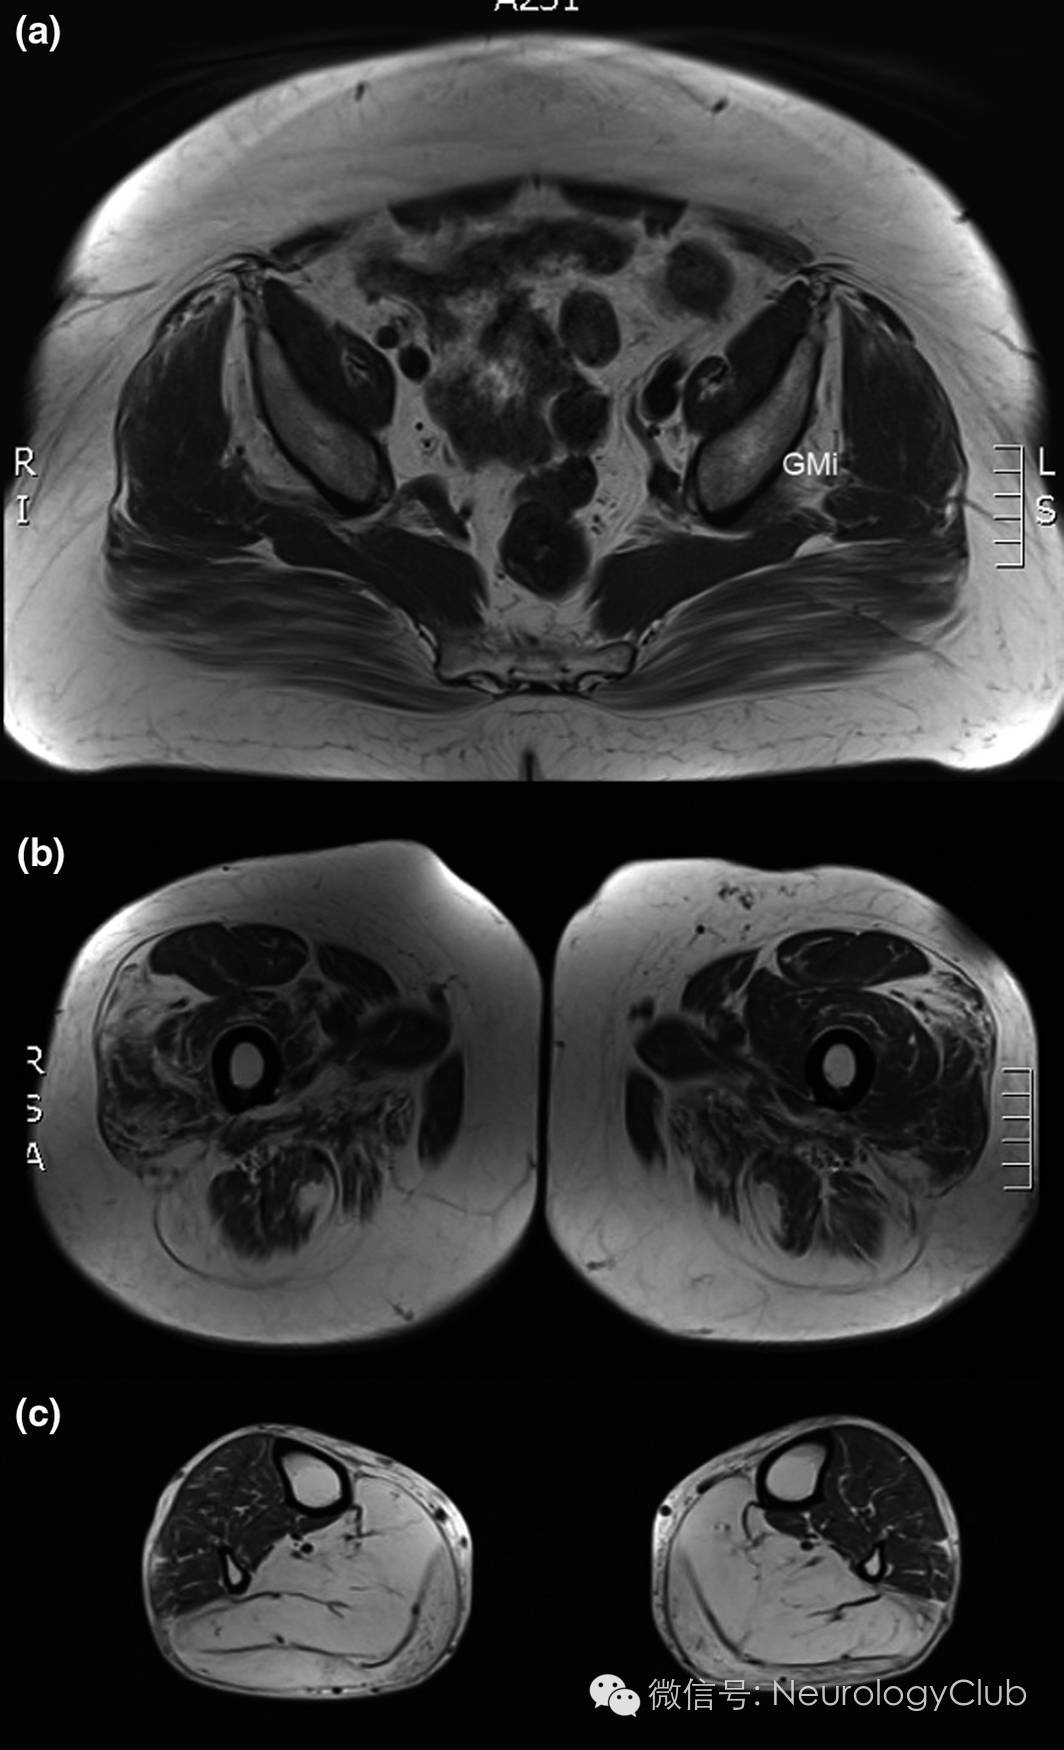

(图2:ANO5突变所致Miyoshi样远端肌病患者的轴位T1WI。骨盆水平可见臀肌的脂肪变性,特别是臀小肌[GMi]已几乎完全被脂肪组织替代[a],大腿水平可见前部和后部肌肉均有受累[b],小腿水平可见腓肠肌脂肪变性[c]